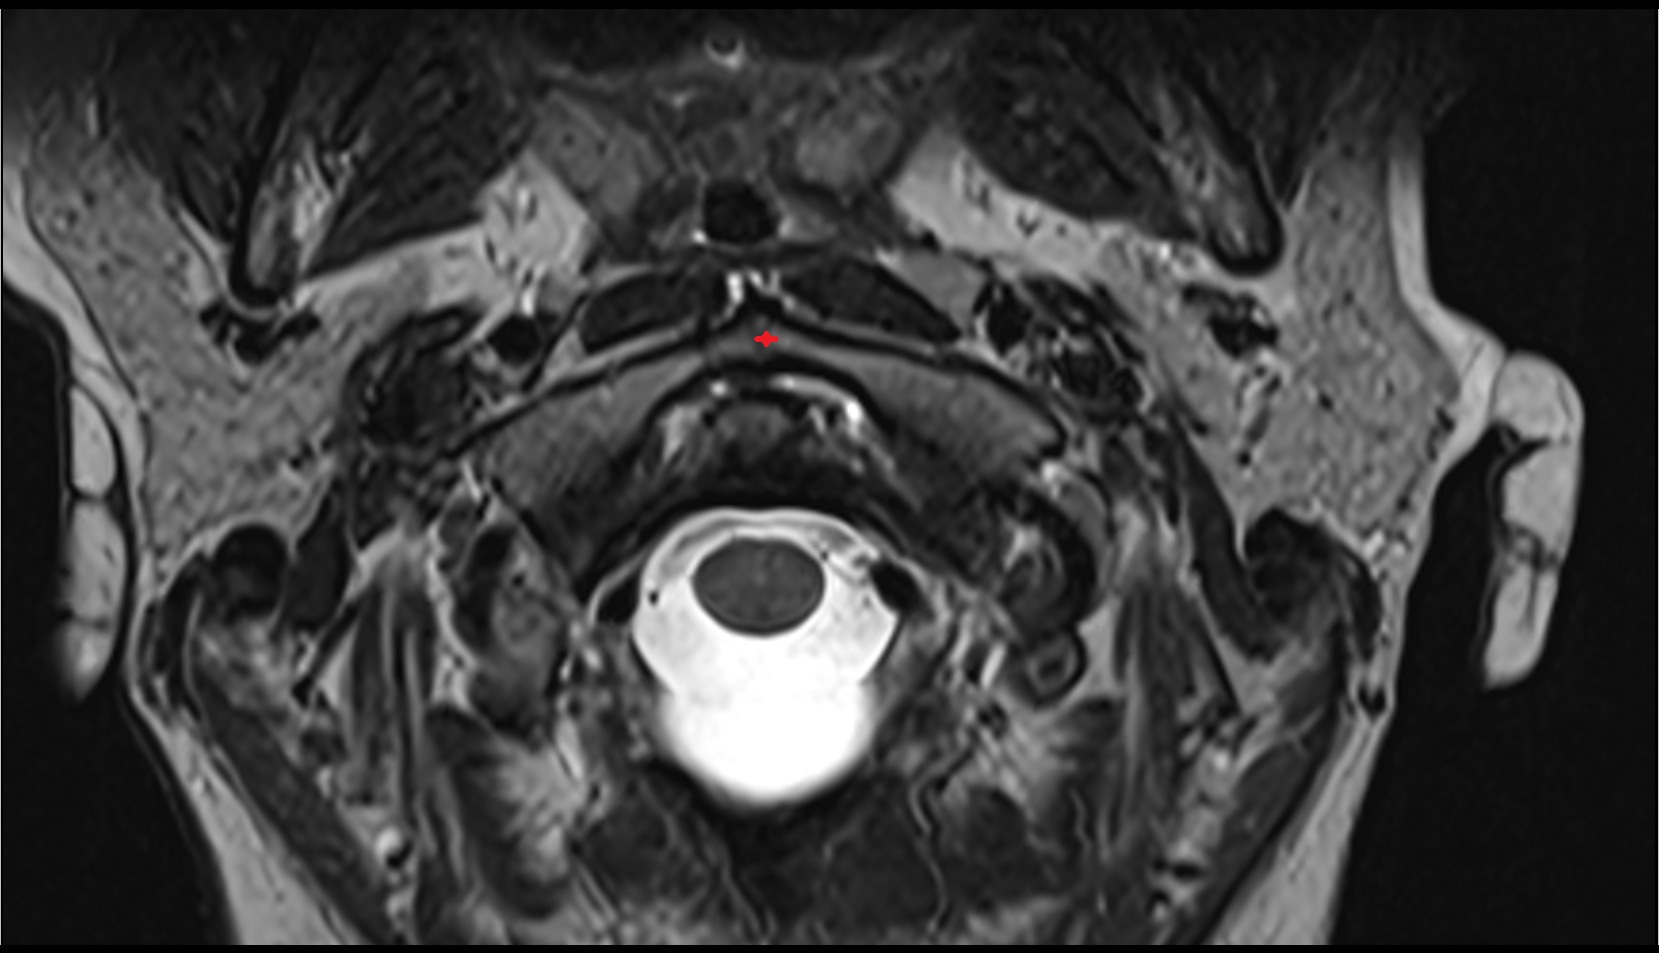

- Peripheral zone of prostate

- Anterior Fibromuscular Stroma of prostate

- Central zone of prostate

- Transitional zone of prostate